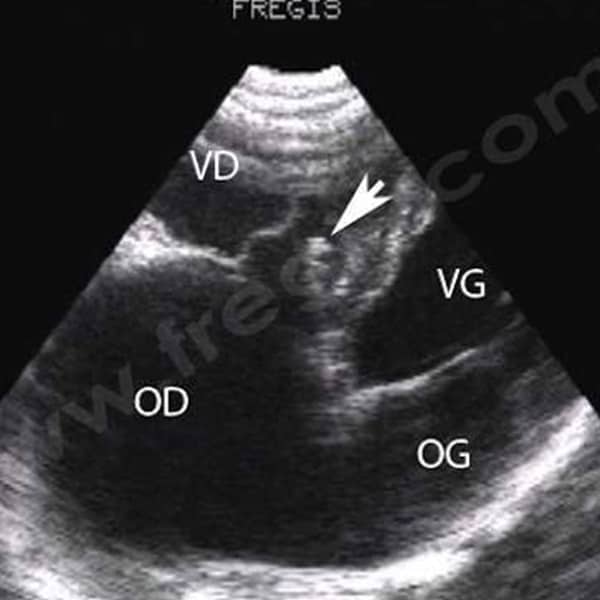

Malformations tricuspidiennes chez le chien